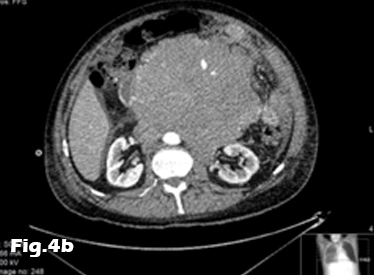

We present the case of a 59-year-old male, previously fit and well who presented to the General Practitioner with a 3 week history of epigastric pain, shortness of breath and unintentional weight loss. On examination, there was evidence of abdominal distension and palpable swelling of left testes. Initial investigation with US of the scrotum revealed dilated (maximally 5.3mm) left pampiniform plexus with retrograde flow on Doppler ultrasound and Valsalva manoeuvre, consistent with an extensive unilateral varicocele (Fig. 1 and 2). Subsequent abdominal ultrasound demonstrated moderate ascites, dilated common bile duct, large right sided pleural effusion and a large 14x14cm solid, vascular epigastric mass. This prompted urgent surgical referral and further cross-sectional imaging (Fig. 3). CT abdomen showed a large soft tissue density retro-peritoneal mass obliterating the portal mesenteric vein circulation and causing the left varicosity (Fig. 4). Ultrasound guided biopsy of the central abdominal mass confirmed a Stage IV Mantle cell Lymphoma.

Figure 4: Contrast-enhanced CT of the abdomen demonstrating the retro-peritoneal mass. Axial images (A, B) of the retro-peritoneal mass encasing the superior mesenteric artery. Sagittal reformatted image (C) of the retroperitoneal mass demonstrating the superior mesenteric artery encasement, the extent of the mass and pleural effusion. Coronal reformatted image (D) of the retroperitoneal mass. Note is made of fluid in the perihepatic space and within the pelvis.